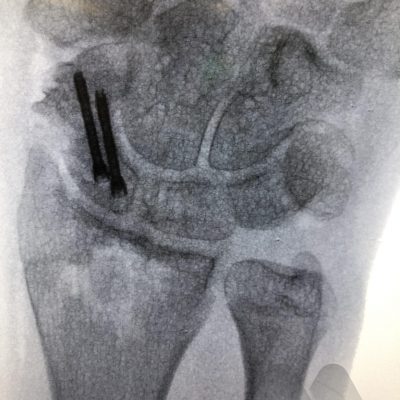

Undisplaced scaphoid waist and distal pole fractures have the best capacity to heal and have a >94% chance of healing even without surgery. They can be managed in a full-time cast or splint for eight weeks. Proximal pole fractures and those that are displaced have a higher risk of the fracture not healing. Proximal pole fractures have a 66% chance of healing by cast treatment and >1mm displacement at the waist, can reduce the healing rate to 73%. In these situations or where full time casting for eight weeks is not desirable, surgical fixation is an option to increase the chance of fracture healing. Depending on the location of the fracture, whether it is fragmented or displaced, will determine how the fracture is fixed. The most common type of fixation is by screw fixation buried inside the bone, inserted through a small incision on the palm near the thumb or back of the wrist.

In situations where scaphoid fractures have been initially missed but identified later, before the onset of arthritis, the diagnosis of a scaphoid non-union is made. These situations often require surgery as the chance of healing by late casting is unlikely to result in fracture healing. The surgery aims to clear out the scar tissue at the fracture site and sometimes add fresh bone from either the wrist or hip to add structural support and fill in defects in the bone and insert a screw for fracture fixation to get the bone to heal and restore normal stability to the wrist. The long term aims are to try and slow the progression towards arthritis in the wrist, however, research studies have shown that this can still develop. In some circumstances where the quality of the bone is poor or has lost it’s blood supply, bone graft with it’s own blood supply is taken from the wrist or knee and connected to the scaphoid.